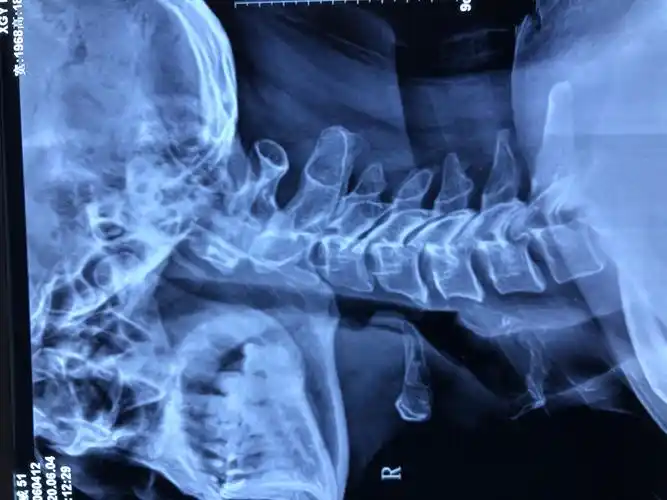

颈椎侧位片